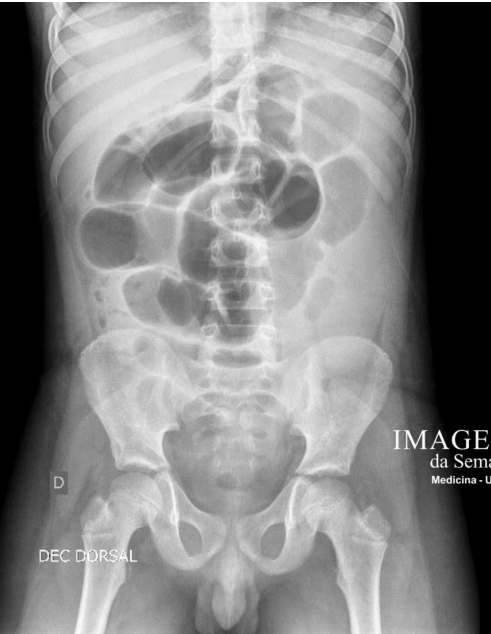

Q

Rotina de imagem de abdome agudo:

A

Tórax PA

Abdome AP ortostático

AP decúbito dorsal

Radiografia rotina no abdome agudo:

Raio x de tórax em PA Raio x de abdome em AP Radiografia de abdome em AP: decubito